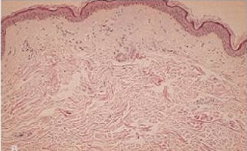

노화가 진행됨에 따라 자연스럽게 피부 진피층의 콜라겐과 탄력섬유의 소실이 일어나며 시작됩니다. 하지만 얼굴의 표정근의 작용으로 생겨나기도 하고 중력에 의해 생겨나기도 합니다.

젊은 피부 노화된 피부